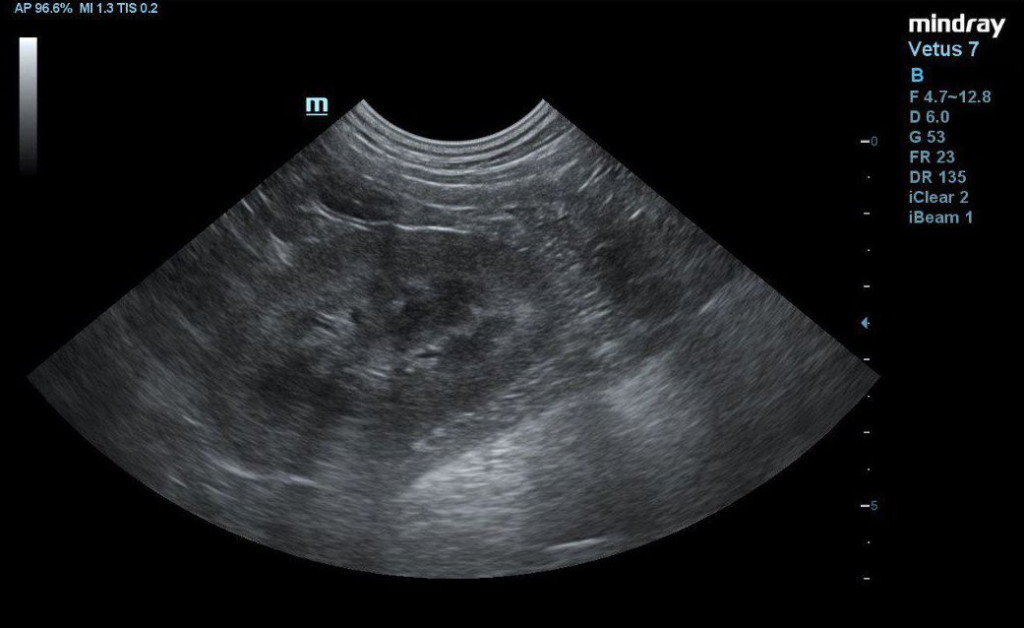

- отсутствие структурных изменений в почках (рис. 4).